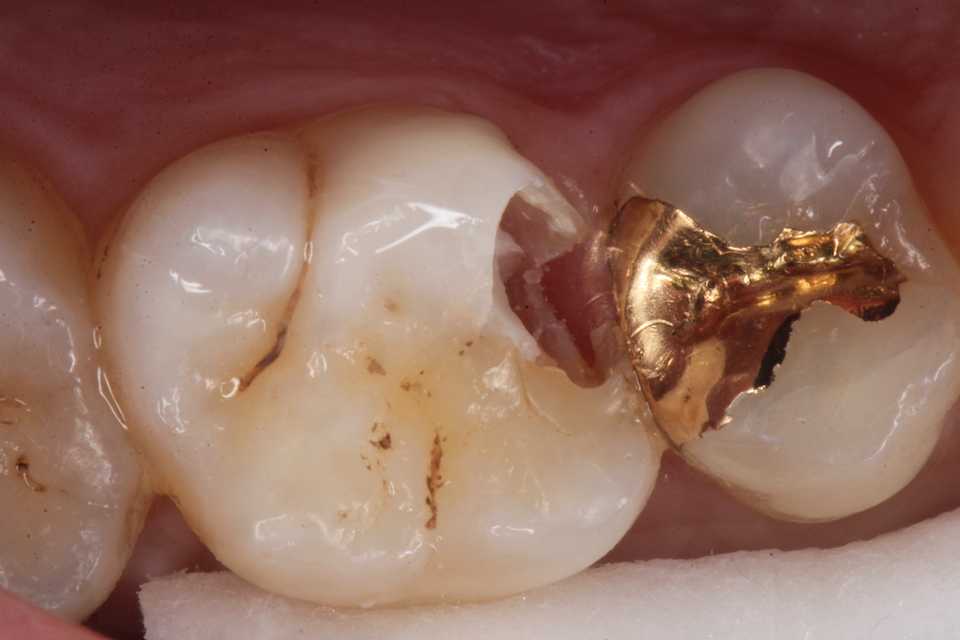

再度3MIX+α-TCPで覆罩してCR充填した。

歯肉縁下に虫歯やクラックが及んでいたができる限り取り除いた。歯肉側のエナメル質は取らざるを得なかったが、これ以上取ると大穴が開く寸前までいった。象牙質のクラックが少し見えるが、α-TCPで治って欲しい。

食いしばり対策にハードタイプのナイトガードも作った。遠くにお住まいの方なのだが、何かあったら飛んで来る!とおっしゃる。

では時系列でどうぞ